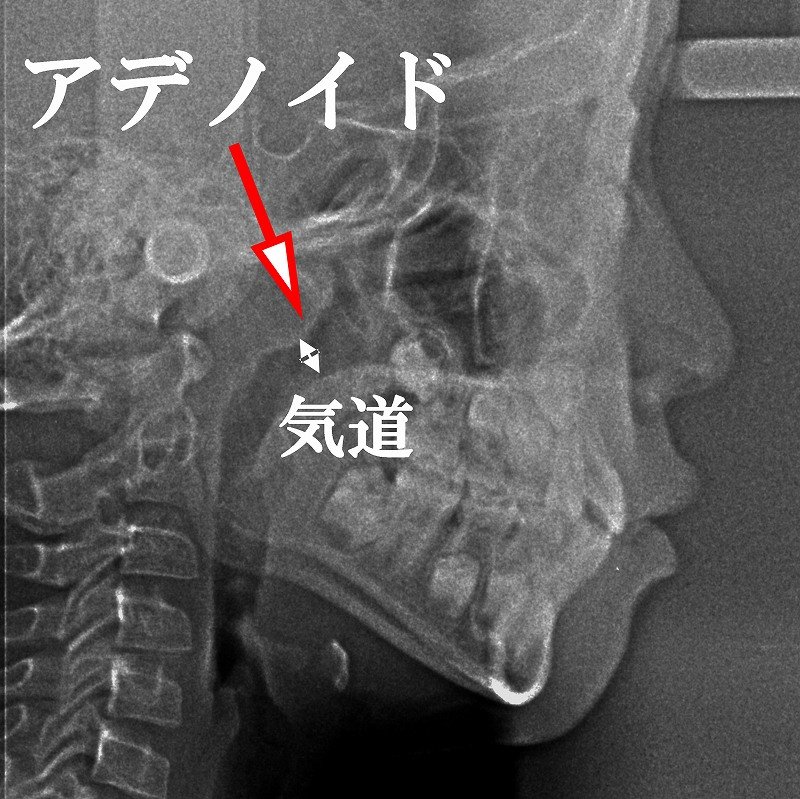

診断

診断は主に耳鼻咽喉科にて行われます。

- 内視鏡検査(ファイバースコープ)

- 側面頭部X線(レントゲン)

- 必要に応じてCT検査

歯科領域では、セファログラムを用いて気道評価やアデノイドの影響を間接的に把握することが可能です。